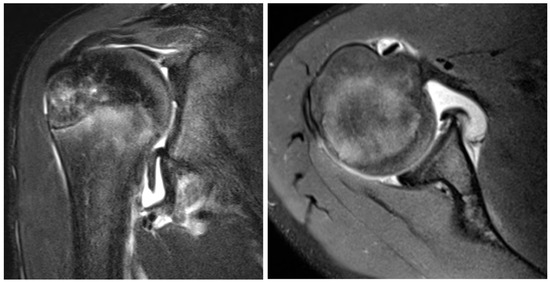

MDI

- Park, K.-J.; Jeong, H.-S.; Park, J.-K.; Cha, J.-K.; Kang, S.-W. Evaluation of Inferior Capsular Laxity in Patients with Atraumatic Multidirectional Shoulder Instability with Magnetic Resonance Arthrography. KJR 2019, 20, 931–938. [Google Scholar] [CrossRef]

- Lim, C.-O.; Park, K.-J.; Cho, B.-K.; Kim, Y.-M.; Chun, K.-A. A new screening method for multidirectional shoulder instability on magnetic resonance arthrography: Labro-capsular distance. Skelet. Radiol. 2016, 45, 921–927. [Google Scholar] [CrossRef]

- Lee, H.J.; Kim, N.R.; Moon, S.G.; Ko, S.M.; Park, J.-Y. Multidirectional instability of the shoulder: Rotator interval dimension and capsular laxity evaluation using MR arthrography. Skelet. Radiol. 2013, 42, 231–238. [Google Scholar] [CrossRef]